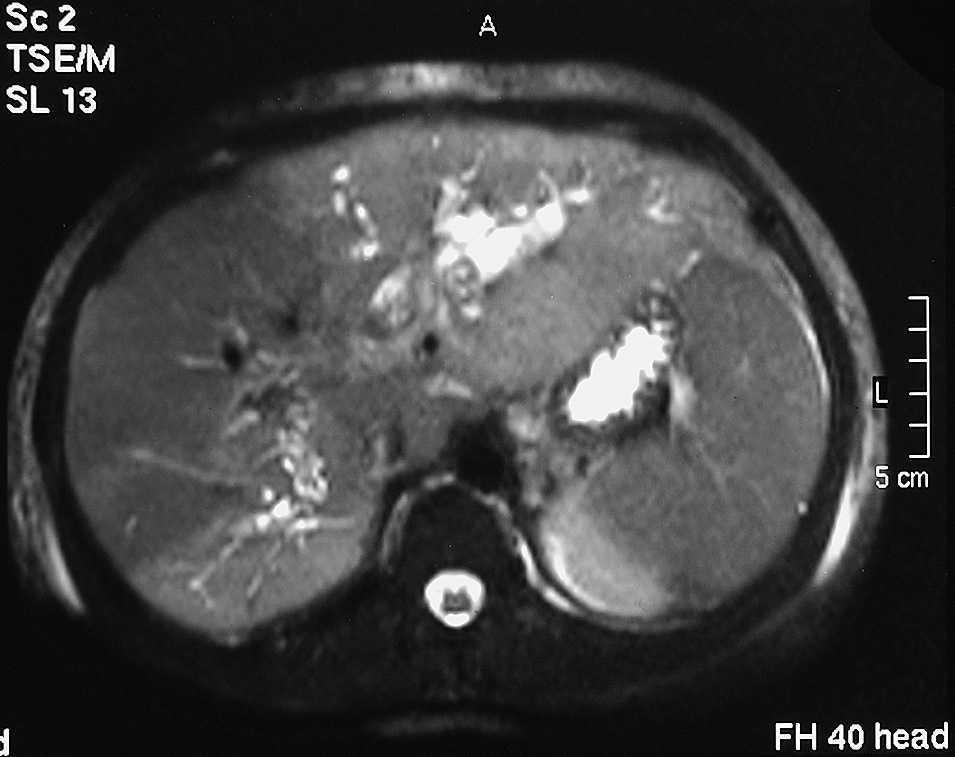

ResultadosEn la tabla 1 se resumen los resultados obtenidos. De los 18 casos registrados, 12 pacientes eran mujeres y 6, varones. La media de edad de aparición de los síntomas fue 45,8 años. La forma de presentación más frecuente fue dolor abdominal (13 casos, 72,2%). En 7 casos (38,8%) la presentación fue en forma de colangitis. Hay que destacar que el caso de adenocarcinoma se inició como hemorragia digestiva alta. El método diagnóstico predominante fue la ecografía abdominal. Hay que destacar que en los casos iniciales de la serie hay un predominio de estudio por colangiografía retrógrada endoscópica, mientras que en los casos más recientes, esta técnica ha quedado en desuso, en beneficio del estudio por colangiorresonancia magnética (fig. 2). En cuanto a los tipos de quiste, hay un predominio de quistes tipo I. El segundo tipo más frecuente es el tipo V o enfermedad de Caroli (fig. 3). En nuestra serie, no hemos registrado ningún caso de tipo III o coledococele. En los 9 casos de quiste tipo I se practicó exéresis total del quiste, colecistectomía y hepatoyeyunostomía en Y de Roux. El único caso tipo II se trató de modo similar, es decir, mediante exéresis del divertículo supraduodenal, colecistectomía y hepatoyeyunostomía. En los 3 casos con quiste tipo IVa se practicó colecistectomía y hepatectomía izquierda, con resección de la vía biliar y hepatoyeyunostomía sobre el conducto hepático derecho.

Fig. 3. Imagen de resonancia magnética de quiste de colédoco tipo V (enfermedad de Caroli) localizado en el lóbulo hepático izquierdo.